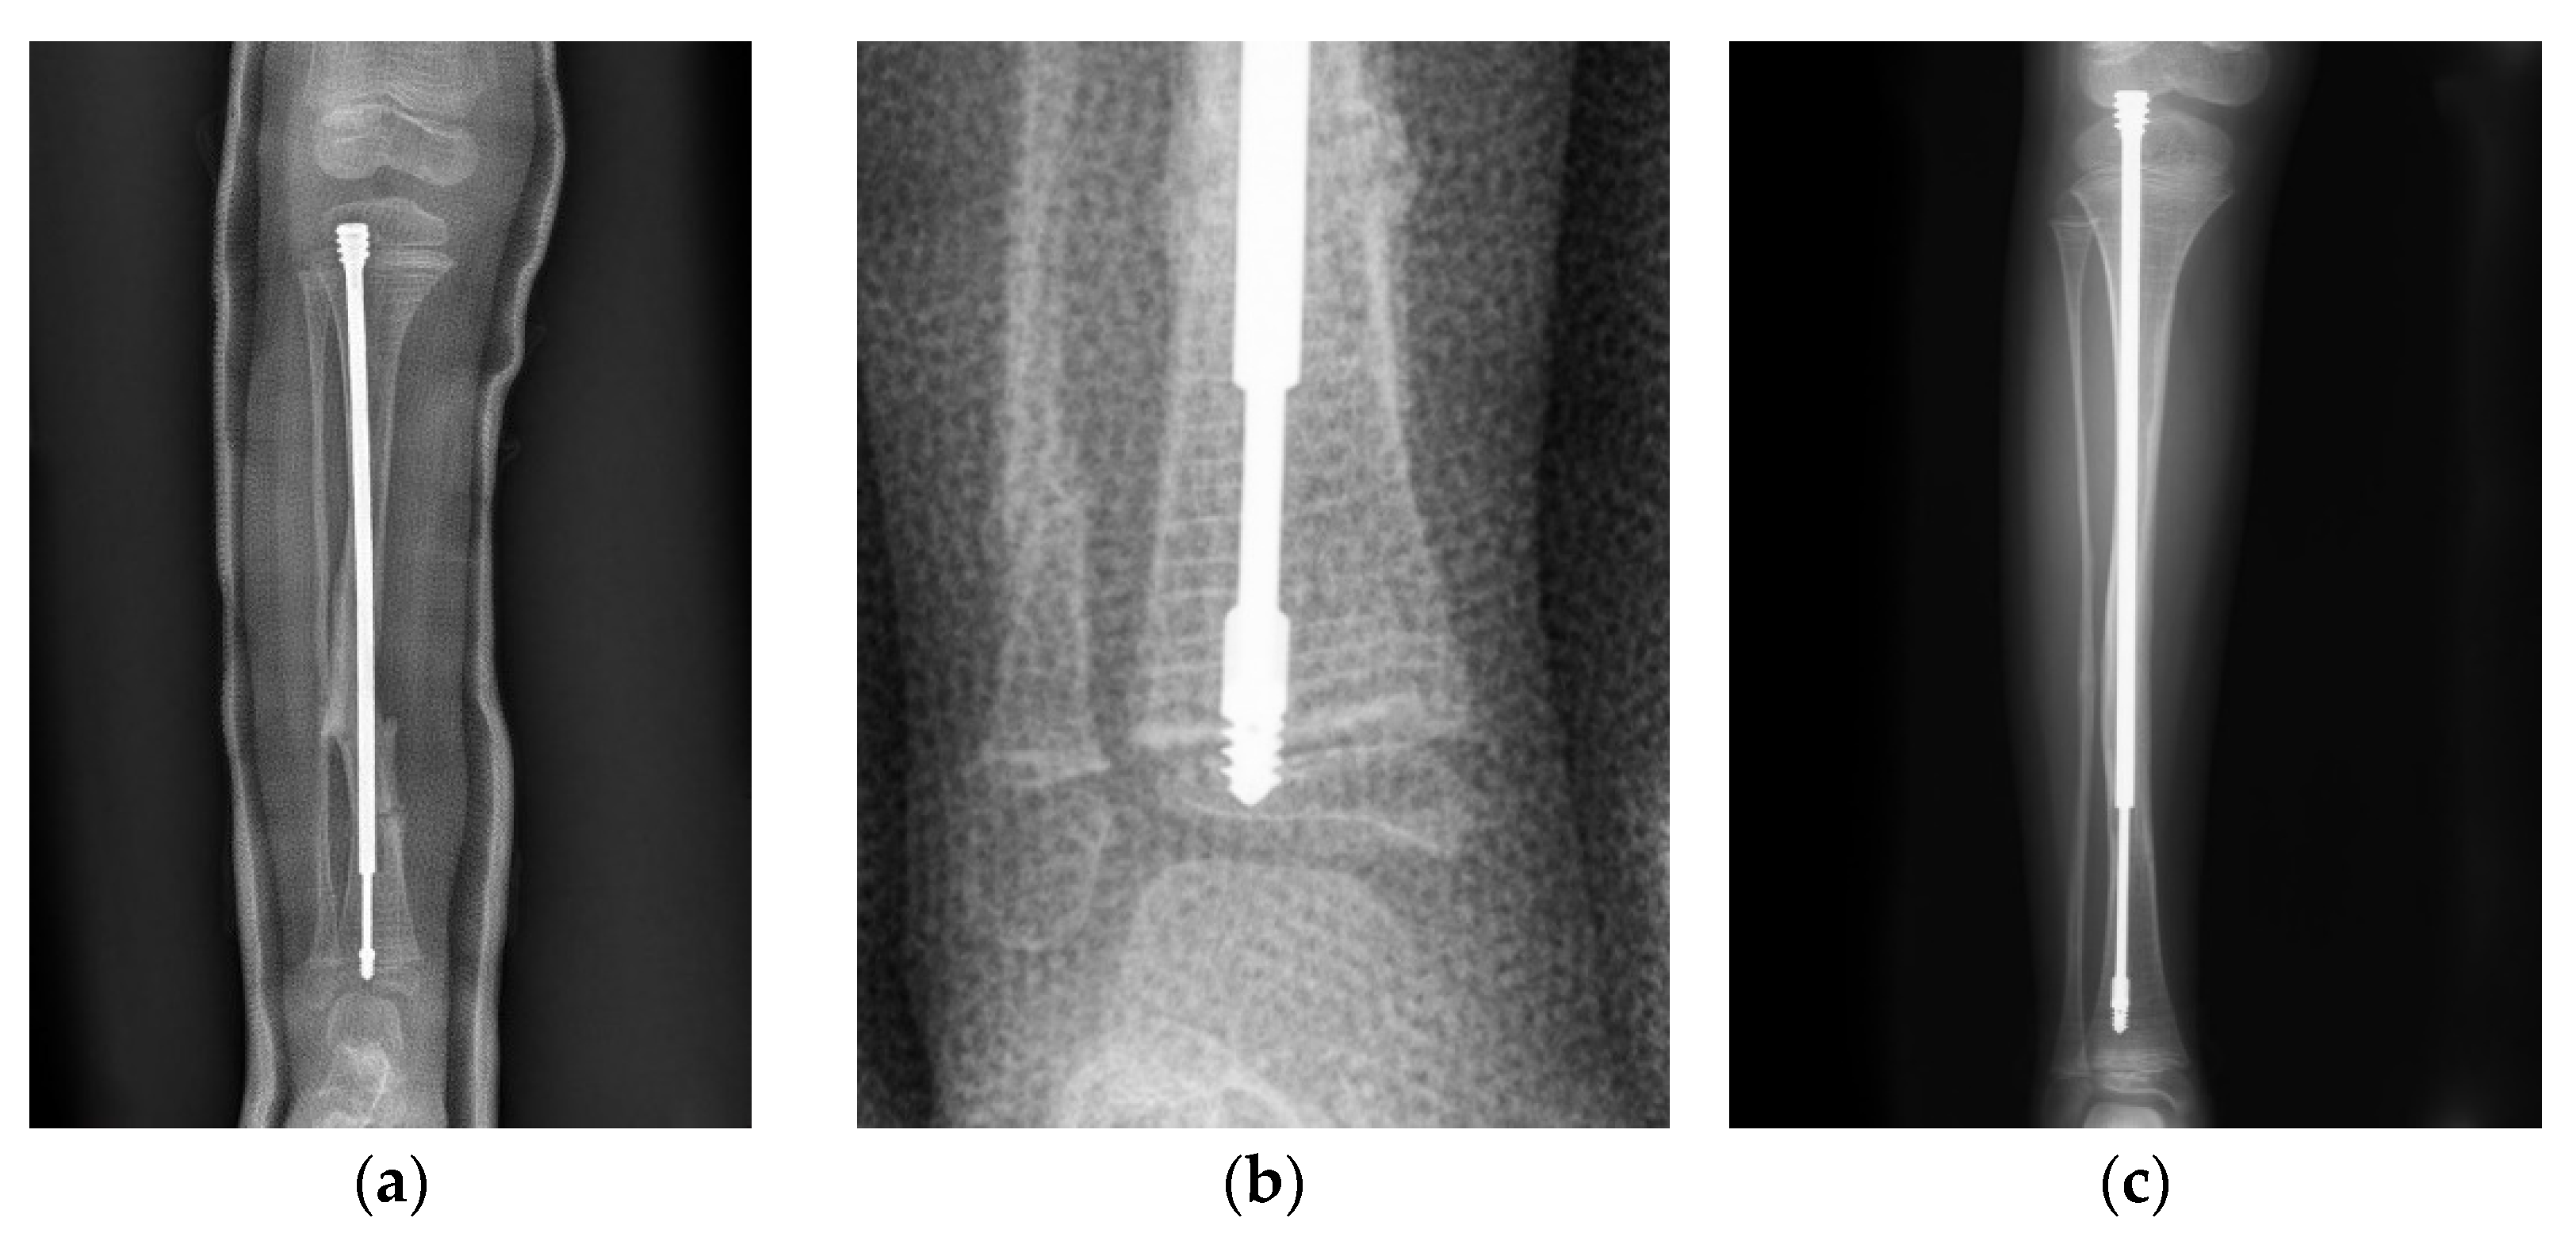

In a case of a 4-year-old female with type III OI (Figure 1), the position of the male component was quite central in the distal epiphysis on both anteroposterior and lateral views. However, there was insufficient purchase of the male component tip (Figure 1a). If the threads end just around the physis instead of beyond it (Figure 1b), distal dislodgement would occur along with growth of the limb (Figure 1c). However, this raises the question of how to ensure sufficient depth of the male implant intraoperatively. We suggest the following steps: First, center the male component at the center of the distal epiphysis as far as possible so that the thickest epiphysis is purchased. The thread of the male component needs to be fully submerged into the epiphysis, and the flange of the nail must exceed the physis, or at least stop at the level of the physis. If the distal epiphysis of the tibia is small, the tip of the nail may reach the subchondral area to ensure that the whole thread goes through the physis (Figure 2). Since the distal epiphysis of the femur is larger than the distal epiphysis of the tibia, there is a relatively lower risk of distal dislodgement in the femur (tibia 4, femur 1 in our series) due to sufficient distal purchase.

Figure 1. Anteroposterior (AP) view radiograph of the lower leg of a 4-year-old female post FD nail implantation. (a) The position of the nail was quite central in the distal epiphysis. (b) Looking closely, there was insufficient purchase of the nail. (c) As the patient grew, the male component migrated (distal tibial nail pulled out of the epiphysis) 1.5 years after implantation.